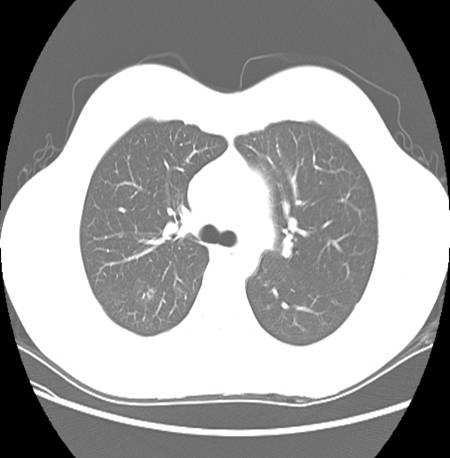

A CT chest was also ordered to further characterize the pulmonary involvement.

Describe chest CT.